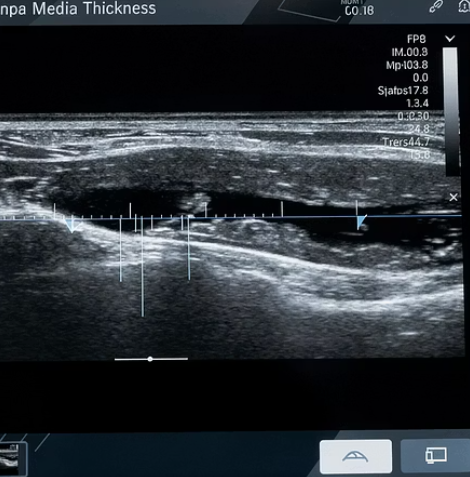

협착증으로 발전하기 전 단계인 동맥경화초음파 소견도 중요합니다. 바로 경동맥의 '내중막 두께(IMT)'를 측정하는 것인데요. 이는 전신 혈관나이측정의 가장 정확한 지표로 통합니다.

IMT가 0.9mm 이상일 경우, 동맥경화가 진행 중임을 의미하며 심혈관 사망률이 2.5배까지 높아진다는 연구 결과가 있습니다. 초음파는 플라크의 상태(안정적인지, 터지기 쉬운 불안정 플라크인지)까지 구분해 주기 때문에 단순한 수치 이상의 정보를 제공해요. 혈관나이측정에 관심 있다면 꼭 확인해 봐야겠죠.